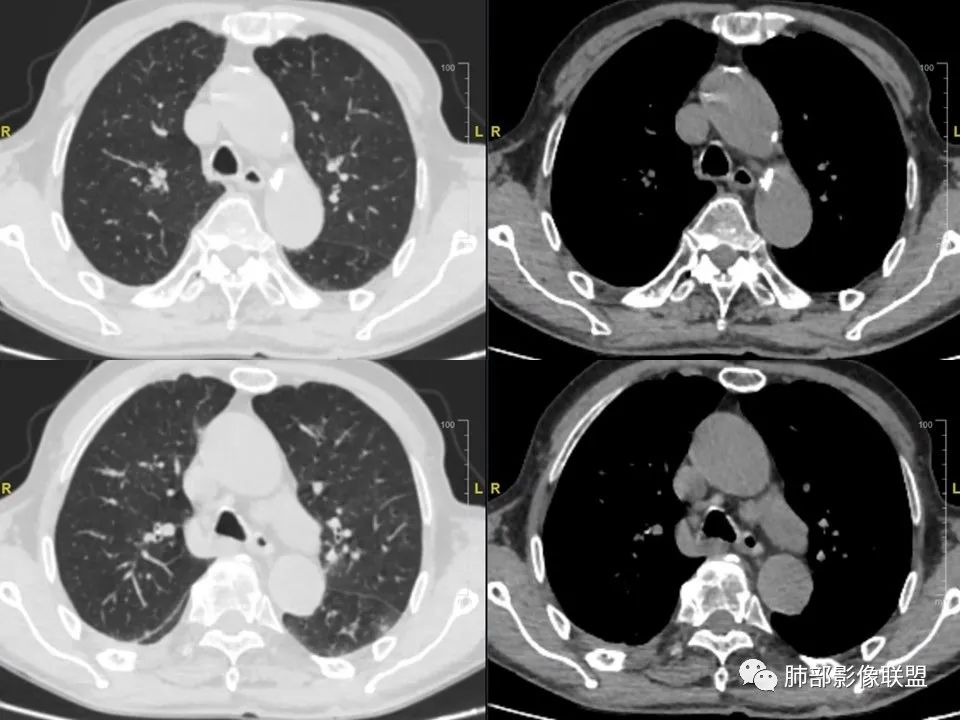

三明治征”之谜—胸膜淋巴瘤1例CT影像

老年男性,右侧胸膜软组织肿块延伸至后纵隔主动脉旁,平扫密度均匀稍高,增强扫描均匀强化,高于肌肉,其内血管走形包绕,部分包绕肋骨,考虑淋巴瘤。病人石棉接触史,不能除外间皮瘤(胸水应该更多)。

右肺下叶肿块,宽基底与胸膜相连,局部胸膜下间隙消失,肋骨未见明显骨质破坏,平扫密度均匀,增强后可见内部点片状强化,坏死囊变不明显,右肺叶裂旁多个小气囊,双肺多发模糊的小结节,老年男性,有石棉肺,综合考虑1:胸膜间皮瘤2:淋巴瘤3:结核瘤4:SFT

右后胸膜下团块,局部膨隆突起,增强扫描有强化,右侧肋间动脉供血,腹膜后主动脉旁亦见团块状软组织密度影,和主动脉分界不清,增强扫描有强化,有石棉工作史,体重明显下降,纵膈淋巴结明显增大,考虑恶性,胸膜间皮瘤?有点疑惑就是胸水不明显,鉴别淋巴瘤。两肺斑片状状影,考虑感染,其中右肺下叶局部结节状影,边缘稍毛糙,周围少许点片状影,首先考虑感染,不除外结核结节和腺癌可能。

石棉接触史,胸膜三明治征,考虑淋巴瘤,鉴别间皮瘤 医学百科网 | YxBaike.Com

肋间动脉漂浮征,淋巴瘤 医学百科网 | YxBaike.Com

黄勇老师讲过,肋间动脉三明治征,淋巴瘤特异性很高。

血管飘浮,三明治,加上纵隔淋巴结多发肿大,部分有融合。基本上定了淋巴瘤了。 医学百科网 | YxBaike.Com

1、老年男性,右侧后胸壁软组织肿块延伸范围较广(至后纵隔主动脉旁),平扫密度均匀稍高,增强扫描均匀强化,其间走行肋间动脉包埋、漂浮(夹心三明治),部分包绕肋骨,肋骨骨质未见明显吸收破坏! 医学百科网 | YxBaike.Com

2、胸膜掀起或尾征,胸壁肋间肌及脂肪间隙浸润,肋间动脉供血。 医学百科网 | YxBaike.Com

3、纵隔淋巴结多发肿大,部分有融合。

4、双侧未见典型胸膜斑,提示石棉非长期接触。胸膜病变不广泛。淋巴结改变与胸膜病灶不相称。 医学百科网 | YxBaike.Com